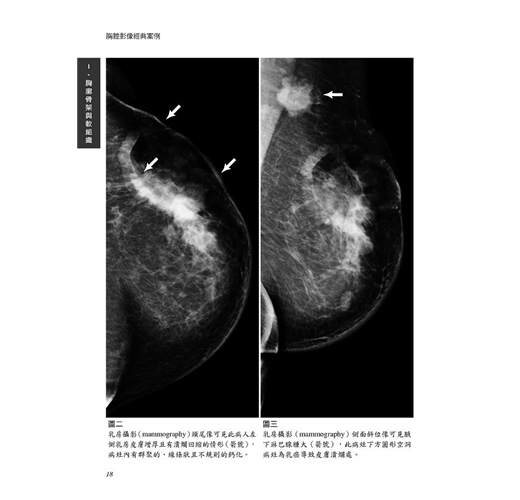

病例4 乳癌合併惡性皮膚潰瘍 17

(Breast cancer with malignant skin ulcer)